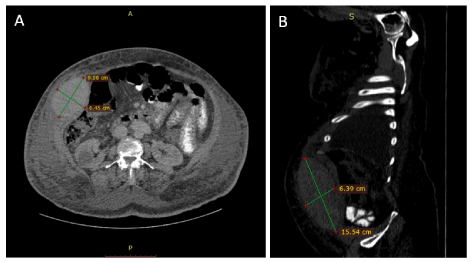

After 48 hours of the paracentesis, the ecchymosis extended to cover the anterior abdominal wall, right anterior chest wall, and the right posterior abdominal wall, in addition to that, the hemoglobin level dropped from 11.2 g/dl to 8 g/dl, and was management by packed red blood cells and fresh frozen plasma transfusion; also CT without contrast for the abdomen was requested and showed a superficial mass in the right lower abdominal quadrant measures about 9 × 6.45 × 15.5 cm (Figure 2).

Figure 2. Non-contrast CT scan of the abdomen. Axial section (A) and sagittal section (B) shows a hyperdense well-localized mass in the right anterior abdominal wall measures about 9×7×15 cm.